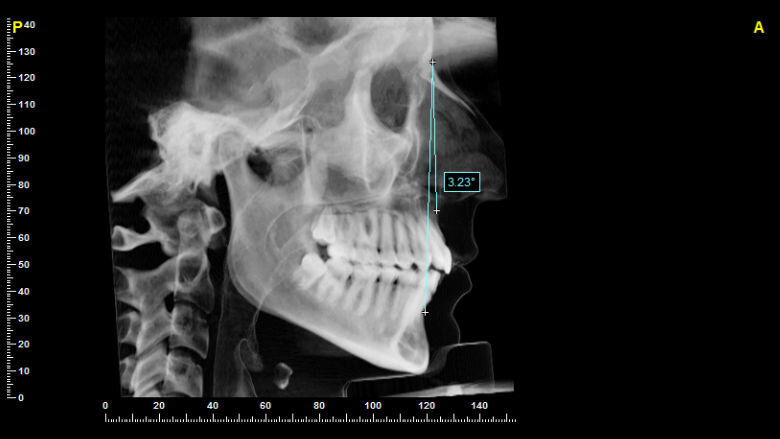

È stato calcolato il valore angolare di ANB su proiezione latero-laterali ottenute mediante sintesizzazione delle scansioni CBCT secondo la tecnica del Ray-Sum elaborata dal software. Grazie al sistema Ray-Sum sono visualizzati, per sommatoria, tutti i valori dei voxel dal punto di veduta al piano di proiezione. Questo numero alla fine viene diviso per il numero stesso dei voxel ottenendo l’immagine finale. Le immagini latero-laterali derivanti dagli esami tomografici sono costruite usando le proiezioni ortogonali settando il centro della proiezione a una distanza infinita dal piano di proiezione come per simulazione di raggi totalmente paralleli tra loro (Fig. 1).

L’identificazioni dei landmark nei cefalogrammi sintesizzati ha una variabilità molto minore rispetto a quella ottenuta dal riconoscimento dei medesimi sui cefalogrammi convenzionali. I soggetti che sono risultati classificabili come I° Classi scheletriche secondo i valori ANB sono stati analizzati secondo la metodica di analisi cefalometrica multiplanare 3D associata a un modulo creato appositamente che prevede lo studio del gruppo incisale superiore.

Fig. 1_Ricostruzione Ray-Sum della Teleradiografia latero-laterale a partire da un esame CBCT.